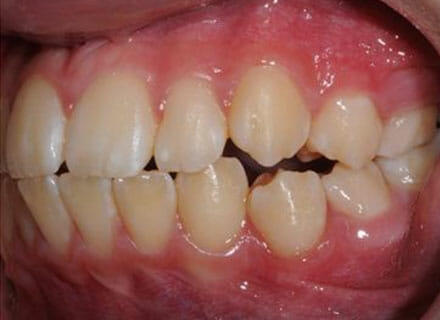

Fixing protruding teeth upper and lower and crowding – no extractions

this patient didn’t like the teeth because they pushed forwards and were sticking out and pushing out her lips. She thought that she looked like she had too many teeth and not enough space. In 12 months we pulled all the teeth back, pulled them together, and lined them all up. No teeth were extracted because we made room by expanding the jaws.